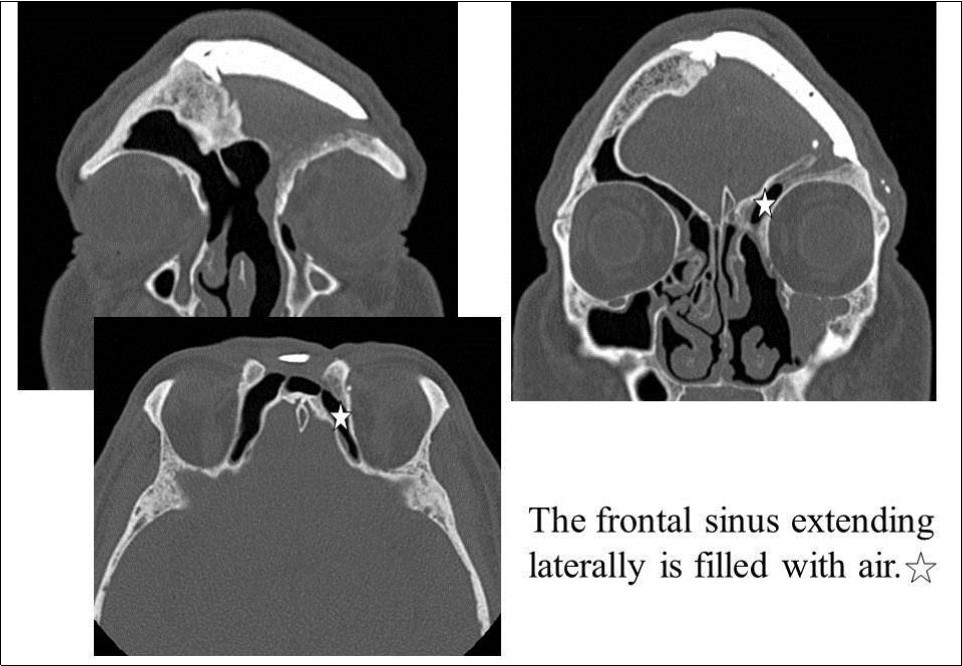

On April 16, 2008, reoperation was performed to place a ceramic implant, but some pus was found in the left lateral sinus. The lesion was debrided, the dead space was filled with muscle, and surgery was completed without ceramic implantation. On October 17, 2008, another surgery confirmed that the frontal sinus was clean, and a ceramic implant was placed. The postoperative course has been good, and as of May 2009, the frontal sinus extending laterally is filled with air (Figure 5, Figure 6).

Figure 5.Paranasal sinus CT after the last surgery. White star: The frontal sinus extending laterally is filled with air.